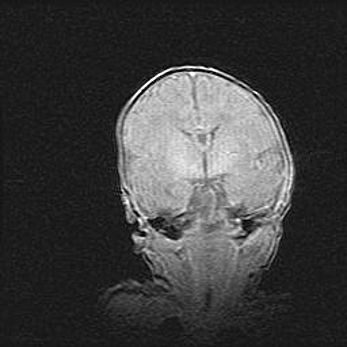

Лейкомаляция с кистозно-глиозной дегенерацией головного мозга.

Возраст: 2 месяца 25 дней

Вес: 6400 г

Окружность головы: 40 см

Срок гестации: 41 неделя

Лейкомаляцию относят к ишемически-гипоксическим повреждениям головного мозга, диагностируемым у новорожденных. При лейкомаляции в головном мозге обнаруживают очаги некроза, возникшие после тяжелой гипоксии и нарушения кровотока. В процессе морфогенеза очаги проходят три стадии: 1) развития некроза, 2) резорбции и 3) формирования глиозного рубца или кисты. Перивентрикулярная лейкомаляция (ПЛ) встречается примерно в 12% случаев среди новорожденных, обычно – у недоношенных детей, причем, частота ее зависит от массы, с которой младенец появился на свет. Наибольшее число малышей страдает лейкомаляцией, если масса при рождении 1500-2500 г.